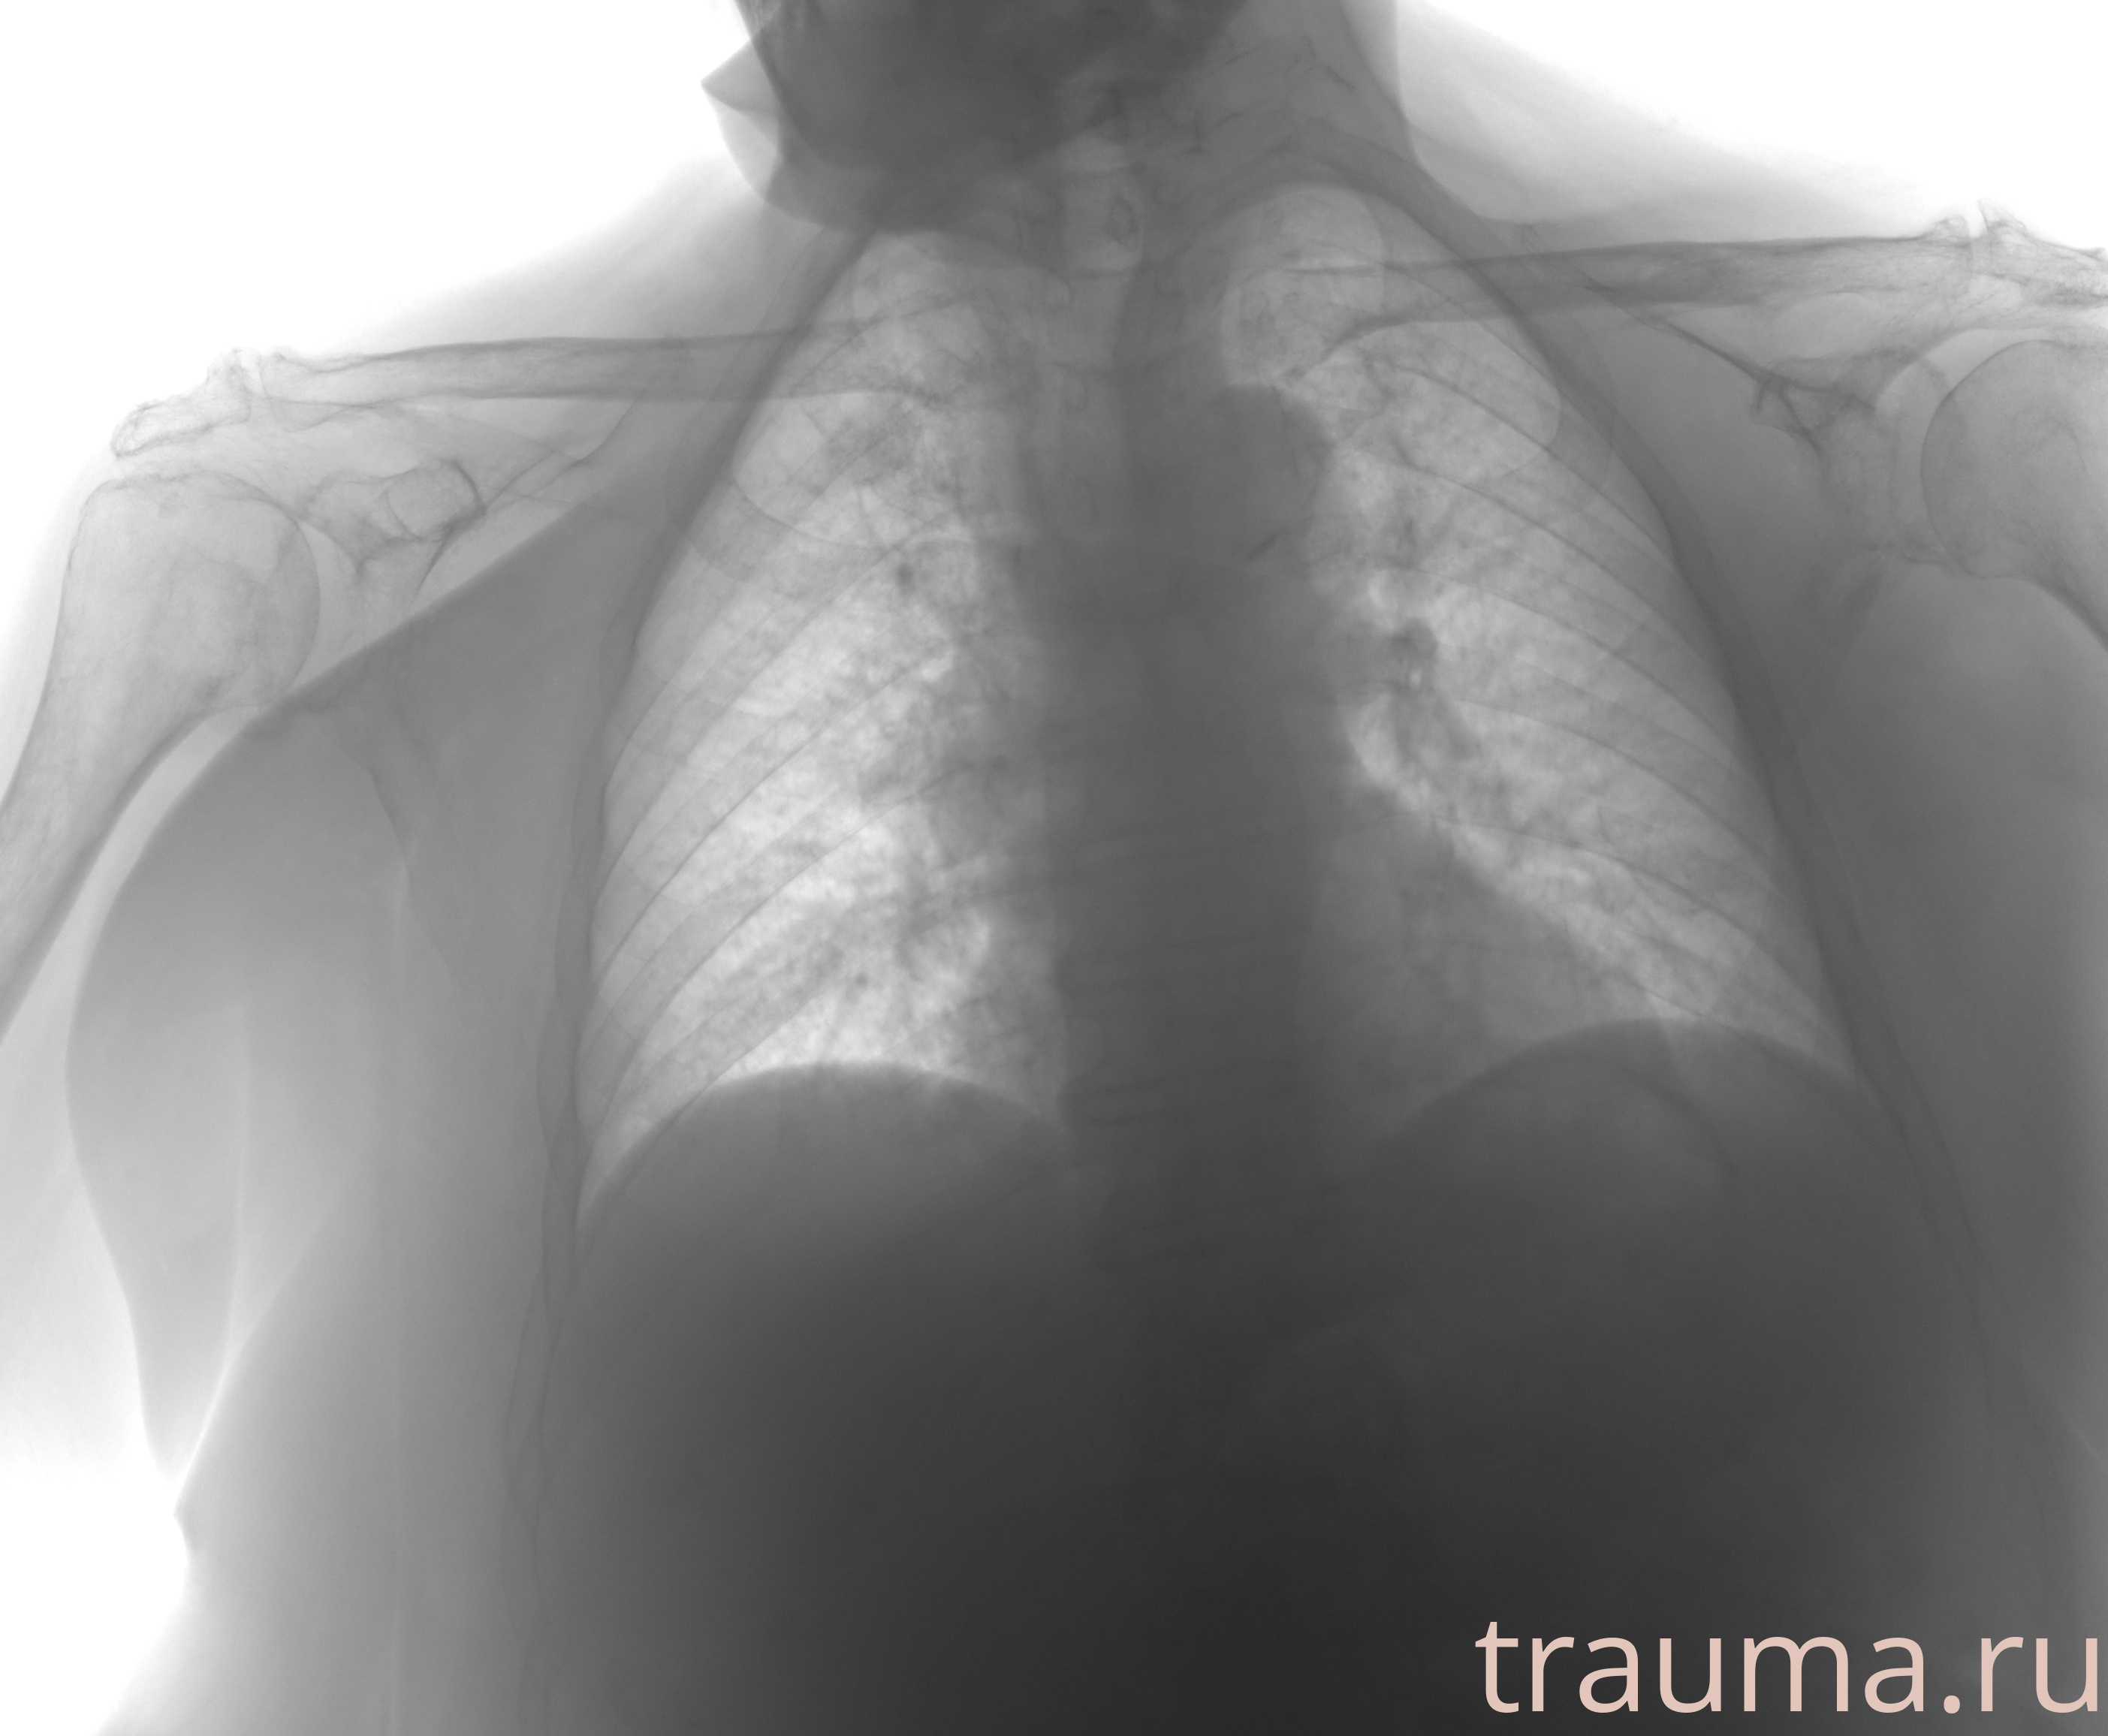

Рентгенограммы

Рентген на дому: по вашему адресу приезжает врач-рентгенолог, травматолог-ортопед с мобильным рентгеновским аппаратом, проводит диагностику травмы или заболевания, делает необходимые рентгенограммы, дает рекомендации по дальнейшему лечению. Получить качественные снимки в домашних условиях возможно благодаря уникальной методике, разработанной МосРентген Центром для института  Склифосовского

при переломе шейки бедра и пневмонии от компании МосРентген Центр - партнера Института имени Склифосовского